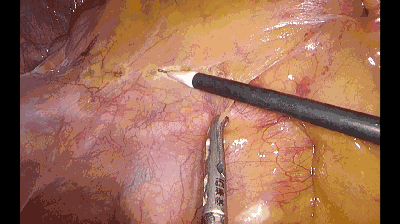

二、挫钩:

要求做到“出手如挫,回手如钩”,所谓“挫”由上而下碾压而进,所谓“钩”,由上而下抓击,实际上走的都是圈。